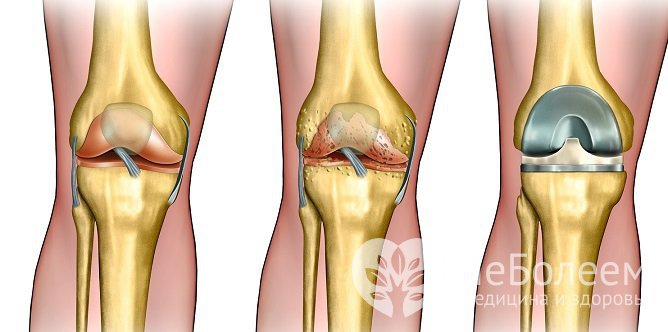

При тяжелом течении патологии проводится эндопротезированиеТяжелые, инвалидизирующие коксартрозы и гонартрозы лечатся эндопротезированием – операцией по замене сустава искусственным.